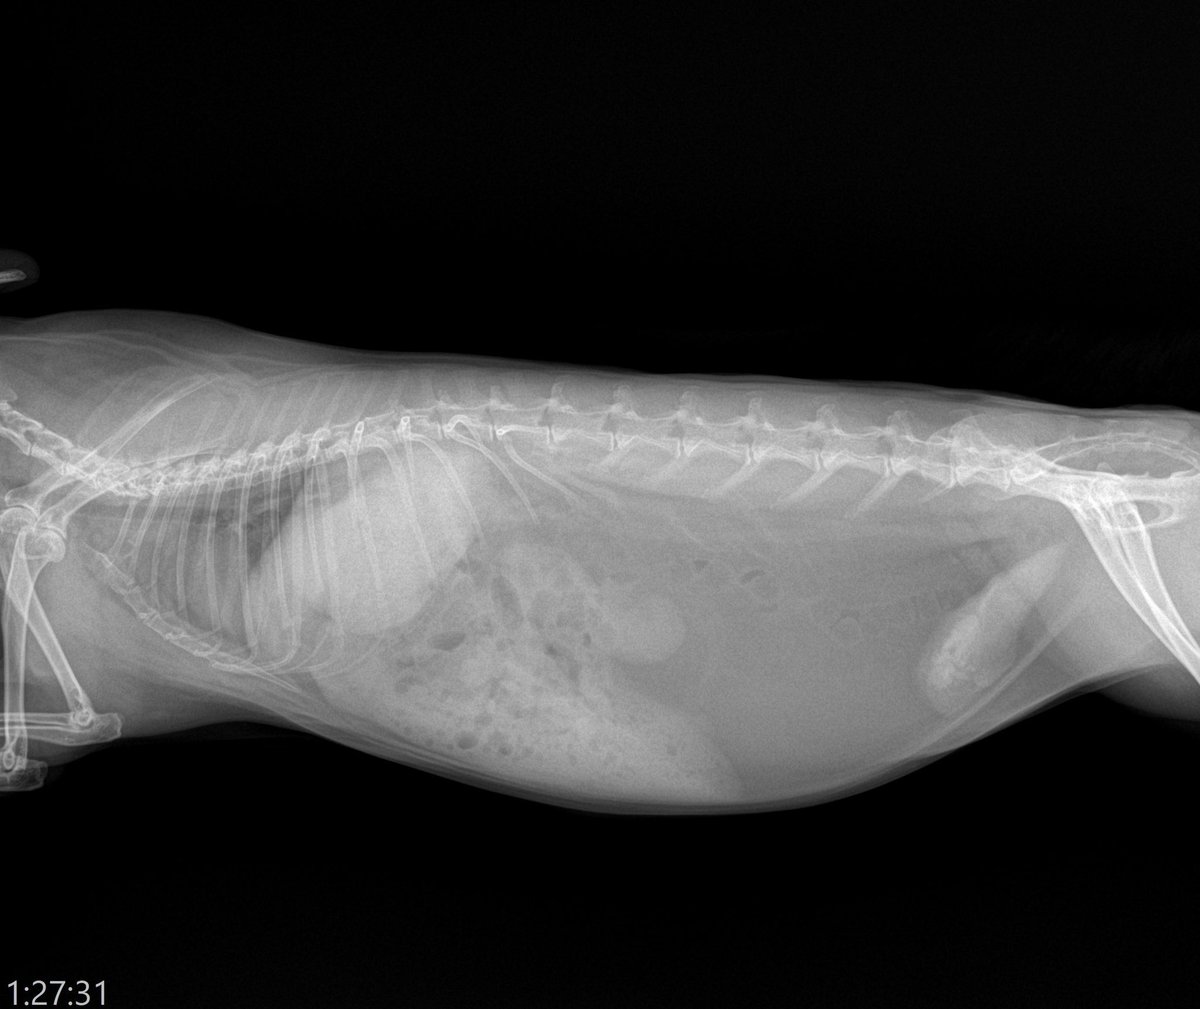

【肥満のうさぎのレントゲン】 レントゲンで空気は黒くポツポツと写るので腸内のガスは健康的な体型の子では黒いポツポツ(青囲い🔵)が腹腔内全体を占めるのが正常になります。(写真1,2枚目)…

レントゲンで空気は黒くポツポツと写るので腸内のガスは健康的な体型の子では黒いポツポツ(青囲い🔵)が腹腔内全体を占めるのが正常になります。(写真1,2枚目)…